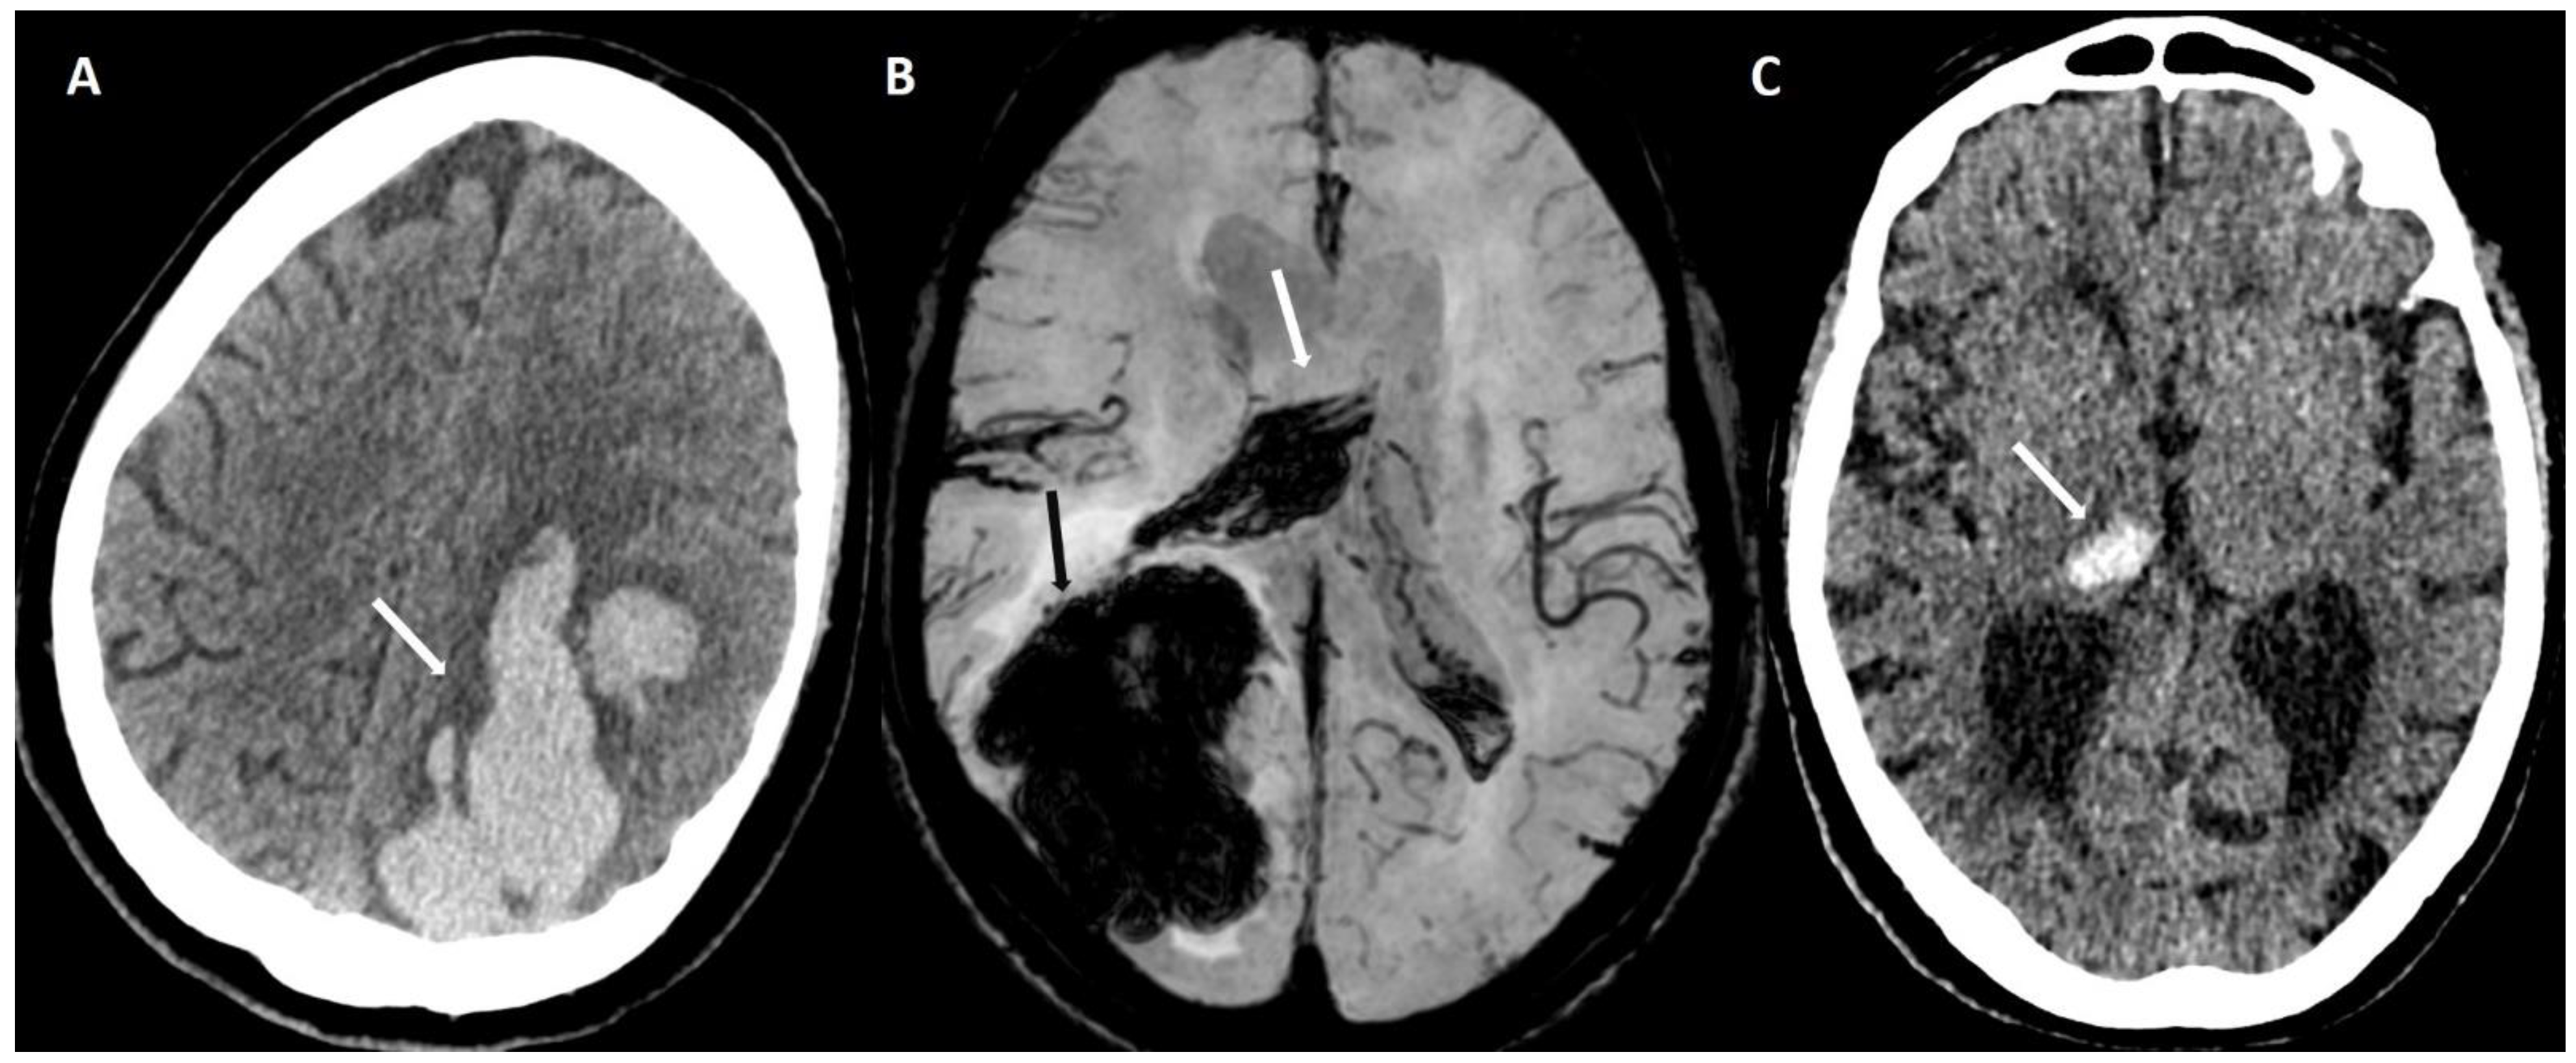

5.1.1. Lobar Hemorrhages

6.1. Finger-like Projections

6.2. Subarachnoid Extension of Lobar Hemorrhage

- Baron, J.-C.; Boulouis, G.; Benzakoun, J.; Schwall, C.; Oppenheim, C.; Turc, G.; Varlet, P. Cerebral amyloid angiopathy-related acute lobar intra-cerebral hemorrhage: Diagnostic value of plain CT. J. Neurol. 2022, 269, 2126–2132. [Google Scholar] [CrossRef]

- Baron, J.-C.; Jensen-Kondering, U.; Sacco, S.; Posener, S.; Benzakoun, J.; Pallud, J.; Oppenheim, C.; Varlet, P.; Turc, G. Can novel CT-and MR-based neuroimaging biomarkers further improve the etiological diagnosis of lobar intra-cerebral hemorrhage? J. Neurol. 2023, 270, 582–588. [Google Scholar] [CrossRef]